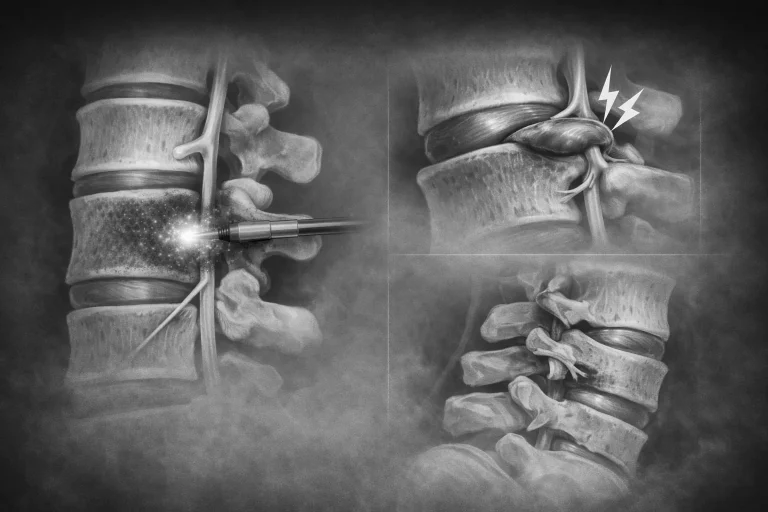

Medical illustration showing spinal procedure with a tool, disc bulge causing nerve pain, and vertebrae alignment.